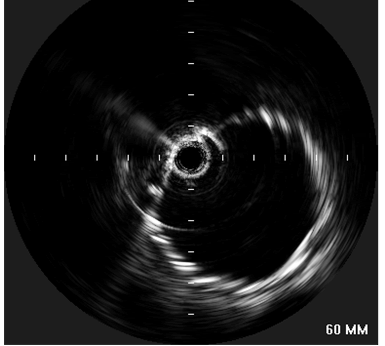

| Figure 4: “Completion”-IVUS examination showing exclusion if the proximal descending aorta. |

concerns about myocardial contusion. After lowering the systolic blood pressure to 100 mmHg, the stent graft was deployed precisely distal to the left common carotid artery. Small boluses of contrast were administered during deployment to confirm device position relative to the left carotid artery. A completion aortogram confirmed adequate exclusion of the transected area and no evidence of an endoleak was identified. A completion IVUS exam was performed, showing complete apposition of the device to the aortic wall circumference (Figure 4). Subsequently, the catheters and the wire were removed from the left groin, and the left common femoral artery is repaired under direct vision. The patient was found to have bounding distal pulses and was neurologically intact after the procedure. The pulses of the left arm were detectable with Doppler. Although the systolic blood pressure in the left arm decreased by 30 mm Hg, the patient did not demonstrate any ischemia or claudication symptoms.